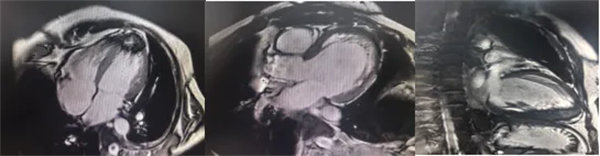

在常规心脏MRI检查中,医学影像科发现患者心肌异常表现,考虑铁过载性心肌病,为明确诊断要进一步加做铁定量技术,加扫T2 mapping序列。CMR铁定量技术是目前评估心肌铁含量的“金标准”,能够快速、无创、精准量化心肌内铁沉积程度,检查结果提示患者局部心肌T2*值显著低于正常范围,符合铁过载性心肌病的诊断标准。

基底部、中间部及心尖部 局部心肌T2*值明显减低T2* 10-20/s, 部分小于10/s

心肌信号局部减低 呈现“黑色心肌”表现,这是由于铁沉积导致局部磁场不均匀,引起信号丢失(失相位)。